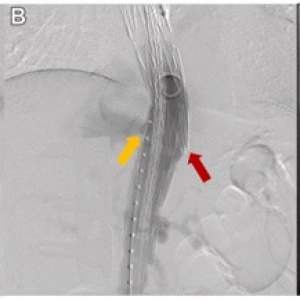

Мужчина, 59 лет

Обратился в отделение неотложной помощи с жалобами на постепенно усиливающуюся боль в спине, которая беспокоила его в течение месяца.

В анамнезе травма грудного отдела позвоночника, полученная в возрасте 42 лет, которая привела к параплегии нижних конечностей и потребовала установки позвоночной пластины. В возрасте 45 лет ему была проведена экстренная операция TEVAR по поводу разрыва инфицированной аневризмы нисходящей части грудной аорты с использованием одностентного трансплантата Najuta (Kawasumi Labo, Inc., Токио, Япония), который состоит из Z-образного стента и ткани из политетрафторэтилена (ПТФЭ). Проведена антибиотикотерапия.

После выздоровления пациент находился под наблюдением в амбулаторных условиях. В течение периода наблюдения его артериальное давление поддерживалось на уровне примерно 130 мм рт. ст. без эпизодов тяжелой гипертензии.

На момент обращения гемодинамические показатели пациента были стабильными: артериальное давление составляло 140/95 мм рт. ст., а частота сердечных сокращений — 110 ударов в минуту.

При осмотре была обнаружена пульсирующая опухоль, пальпируемая примерно на расстоянии трёх пальцев ниже кончика левой лопатки.

📌 Из-за изменений в алгоритмах ВКонтакте мы вынуждены публиковать только анонсы.

Обратился в отделение неотложной помощи с жалобами на постепенно усиливающуюся боль в спине, которая беспокоила его в течение месяца.

В анамнезе травма грудного отдела позвоночника, полученная в возрасте 42 лет, которая привела к параплегии нижних конечностей и потребовала установки позвоночной пластины. В возрасте 45 лет ему была проведена экстренная операция TEVAR по поводу разрыва инфицированной аневризмы нисходящей части грудной аорты с использованием одностентного трансплантата Najuta (Kawasumi Labo, Inc., Токио, Япония), который состоит из Z-образного стента и ткани из политетрафторэтилена (ПТФЭ). Проведена антибиотикотерапия.

После выздоровления пациент находился под наблюдением в амбулаторных условиях. В течение периода наблюдения его артериальное давление поддерживалось на уровне примерно 130 мм рт. ст. без эпизодов тяжелой гипертензии.

На момент обращения гемодинамические показатели пациента были стабильными: артериальное давление составляло 140/95 мм рт. ст., а частота сердечных сокращений — 110 ударов в минуту.

При осмотре была обнаружена пульсирующая опухоль, пальпируемая примерно на расстоянии трёх пальцев ниже кончика левой лопатки.